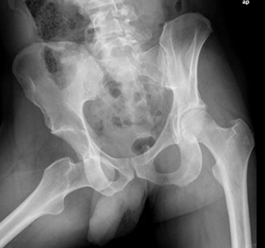

Fig 66. Luxación anterior de cadera.

Rx AP. Luxación anterior con desplazamiento anteroinferior de la cabeza.